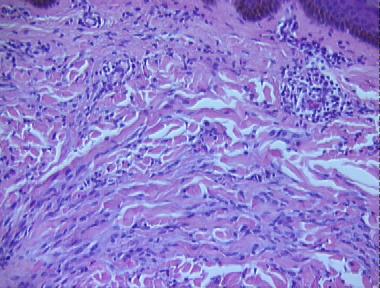

Histologic Features

- An inflammatory process diffusely involving the upper dermis and abutting against the epidermis, characterized by

- A moderately dense lymphocytic infiltrate around vessels and adnexae

- Many spindle fibroblasts between collagen bundles in association with mucin deposition and mast cells

- Some fibroblasts in stellate-shapes

- Fibroblasts in fascicular formation and an increased collagen deposition

- Prominent fibrosis of the reticular dermis and pannicular septae